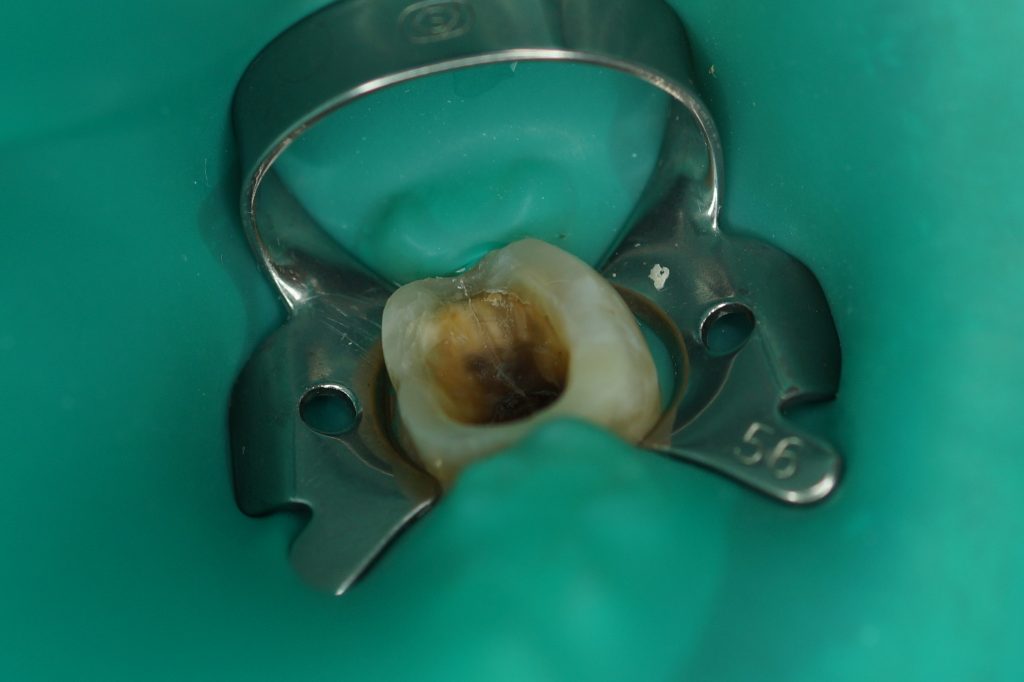

- Artykuł przedstawia przypadki kliniczne, w których rozpoznano zespół pękniętego zęba, wtórny do urazu okluzyjnego.

STRESZCZENIE: Artykuł przedstawia przypadki kliniczne, w których rozpoznano zespół pękniętego zęba, wtórny do urazu okluzyjnego.

Zespół pękniętego zęba (cracked tooth syndrome, CTS) został opisany i zdefiniowany po raz pierwszy w 1976 roku przez Camerona (1). Opisany jest jako niecałkowite pęknięcie zęba z żywą miazgą obejmujące swoim zasięgiem zębinę i prawdopodobnie miazgę zęba. Objawy sugerujące wystąpienie syndromu pękniętego zęba to ból na nagryzanie podczas spożywania zimnych i gorących pokarmów. Nacisk okluzyjny podczas żucia powoduje ruch odłamów względem siebie, co z kolei powoduje rozprzestrzenianie się pęknięcia aż do miazgi zęba, wywołując stan zapalny spowodowany mikroprzeciekiem bakteryjnym. Rozprzestrzenianie się zapalenia prowadzi do nieodwracalnego zapalenia miazgi wymagającego leczenia endodontycznego. Wśród przyczyn powodujących występowanie pęknięć w obrębie [...]